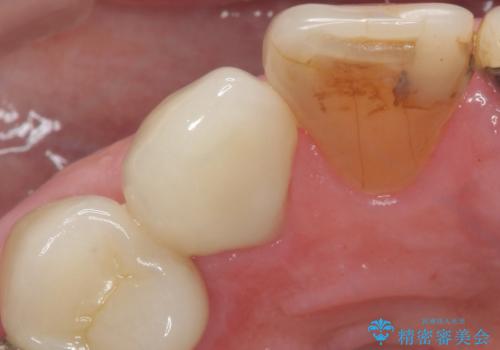

クラウンでの修復は歯の形を変えある程度すき間を埋めることが可能です。

歯と歯の間の大きなすき間と虫歯の両方を解決することができ、大変満足していただけました。